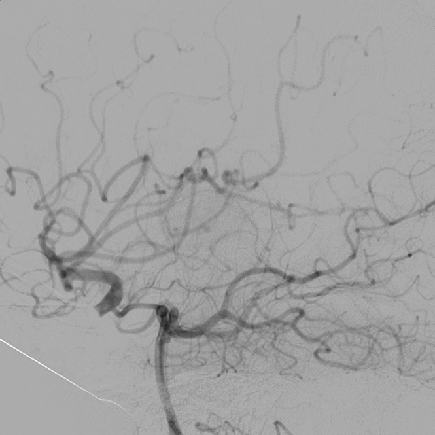

2014-9-29 DSA